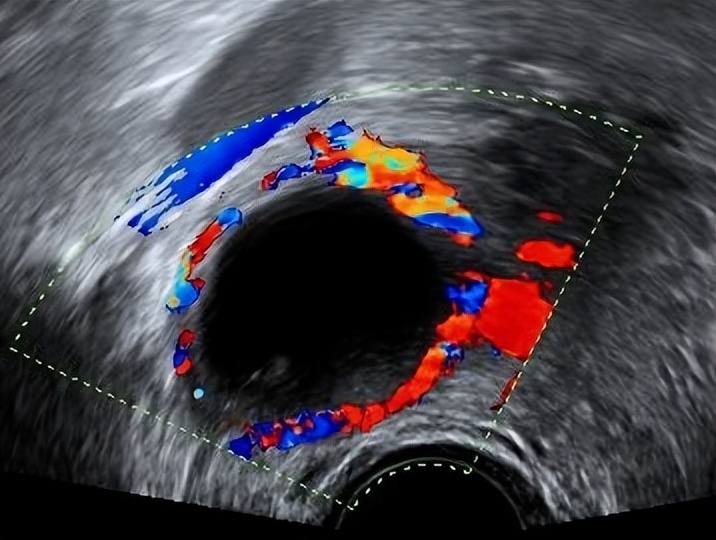

02、 黄体囊肿

卵泡正常排出卵子后,会演变为黄体,正常直径为2~3cm,若黄体内毛细血管出血或液体积聚,则形成黄体囊肿。

黄体囊肿多发生于月经周期的后段(第14~28天),由于这种囊肿会持续分泌孕激素,可能导致月经推迟。一般来说黄体囊肿会自行消退。但极少数会发生破裂,引发下腹疼痛和盆腔内出血,此时需要及时就医,根据严重程度来决定保守治疗或手术治疗。